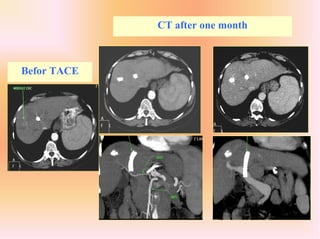

CT after one month

CASE 2 :

- woman of 62 years with cirrhosis viral C, Child A

- TIPS for recurrance UDH

- Smalle HCC of 3 cm in segment 8

Hyper selective TACE of segment 8

Befor TACE